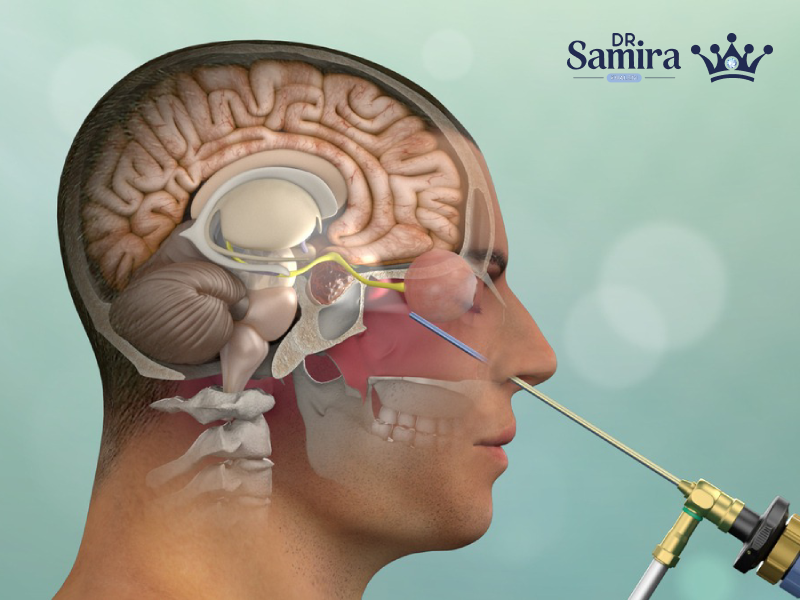

انواع آدنوم هیپوفیز موضوعی مهم در غدد درونریز و نورولوژی است، چون این تومورها با اینکه...